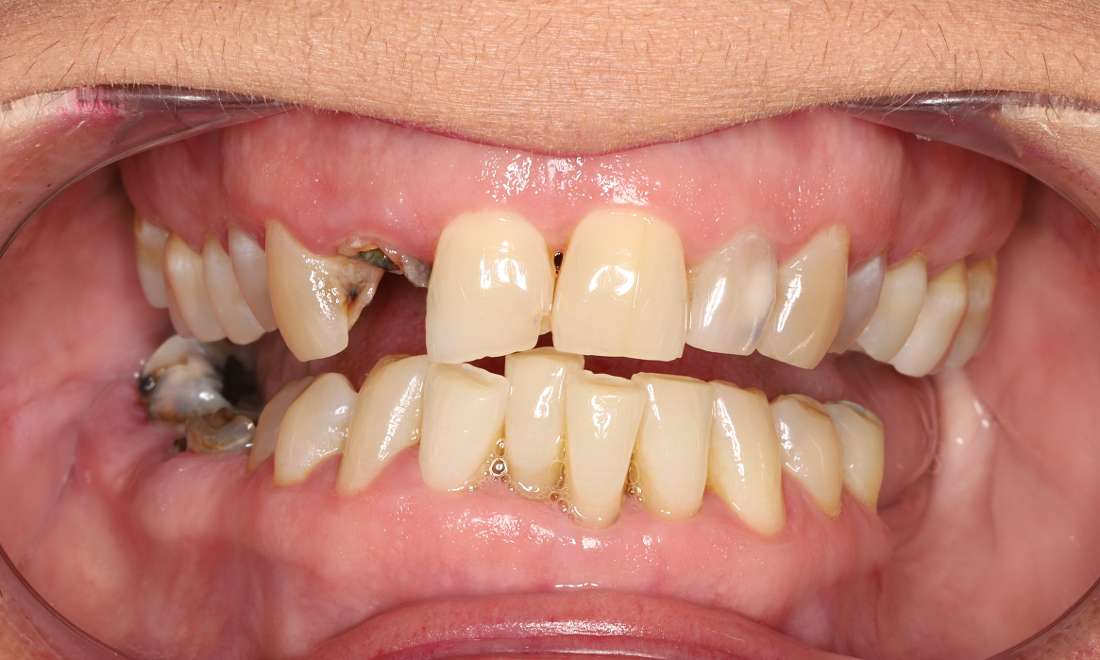

Upper Arch Reconstruction with Crowns and Bridges

Dental anxiety prevented this wonderful patient from seeking our help until her pain was unbearable. Her anxiety was addressed with a combination of oral sedation, nitrous oxide, and our caring team focused on addressing her needs in a calm, comfortable environment.

Over several well-planned visits, we were able to remove hopeless teeth, complete initial gum disease treatment, complete root canals on teeth with pain and infection, and then make long term 3D printed temporary crowns and bridges to test out her newly established bite. Missing teeth on the lower arch will be replaced with dental implants in the future.